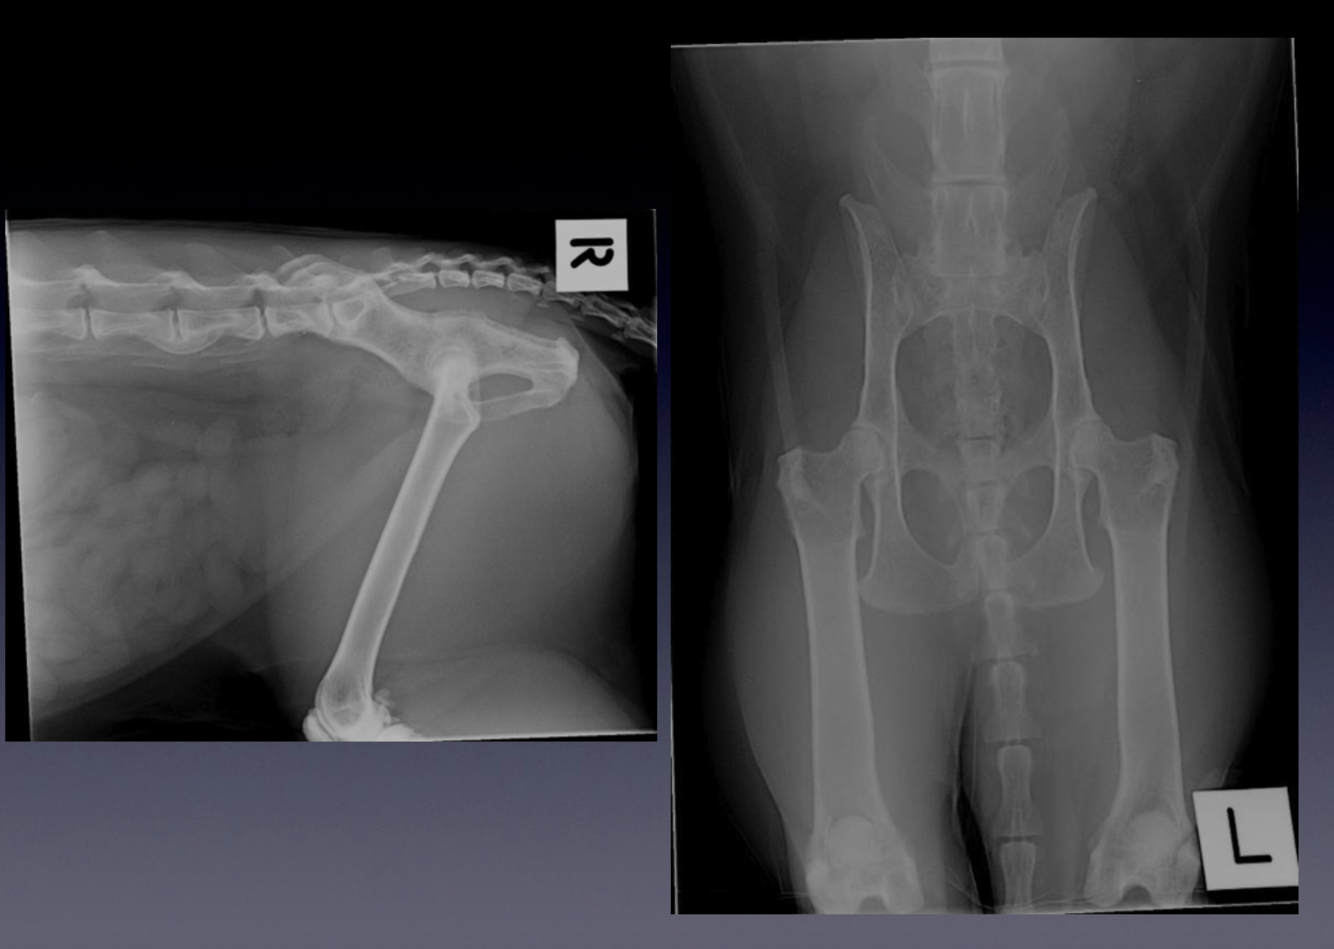

Patient number 242727 - Normal Hip and Elbow Screening Radiographs

These radiographs were taken to screen the patient for the presence of hip and elbow dysplasia.

VIEW?

Notice:

1.

The collimated field includes the entire pelvis and femoral condyles/stifle joints

2.

The symmetry of the pelvis, with similar appearance to the iliac wings and symmetric size of the obturator foramina

3.

The femurs are parallel

4.

The patellas are superimposed over the femoral trochlea.

5.

These radiographs are normal, but when evaluating hip radiographs:

note the congruence of the coxofemoral joints

look for evidence of osteoarthritis

6.

These factors are considered when allocating a final hip ‘score’.

The elbows are taken as mediolateral projections with the elbows in full flexion.

The medial and lateral portions of the humeral condyle are superimposed, forming parallel curved surfaces.

When the elbow is in full flexion, the anconeal process is readily visible.

These elbows are normal, but in a patient with elbow dysplasia there will be early signs of arthritis

osteophyes on the anconeal process

sclerosis of the ulna trochlea notch

In more advanced cases of arthritis, osteophytes are seen associated with all aspects of the elbow joint

The pelvis view is a ‘Ventrodorsal, hip extended’ projection.